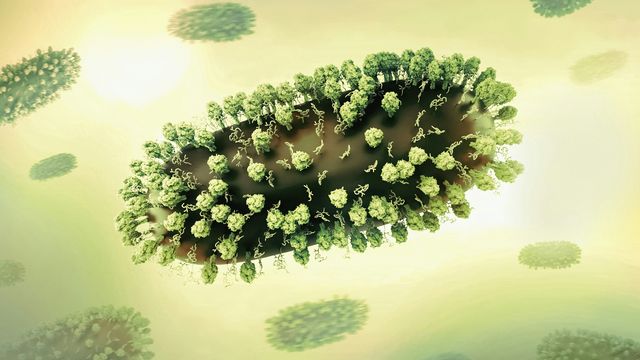

COVID Infections Trigger Virus-Induced Inflammation During Pregnancy

A new study shows that mild SARS-CoV-2 infections during pregnancy can trigger immune responses that cause inflammation in a developing fetus.